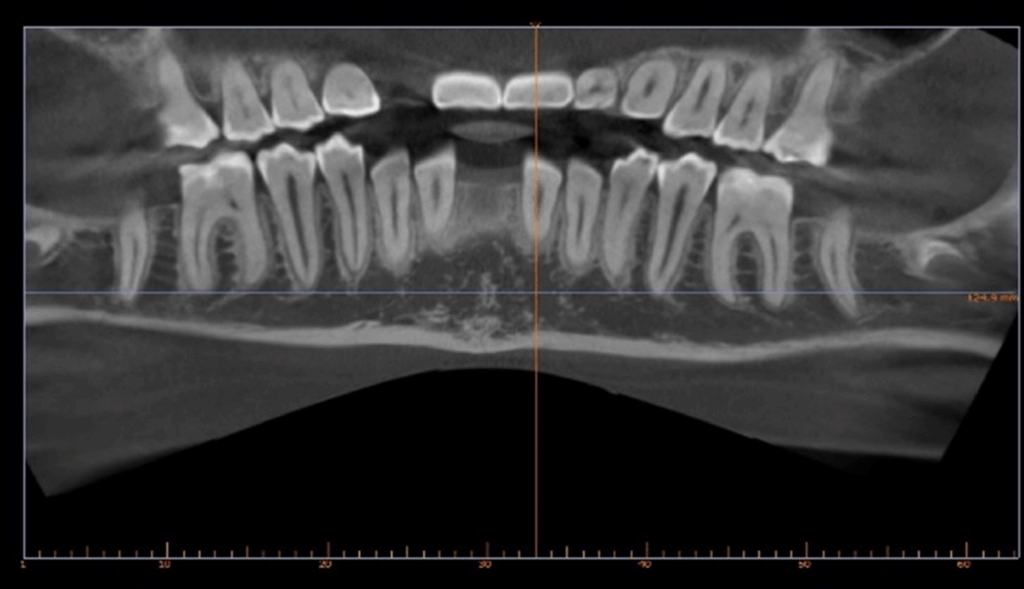

Skeletal Class II due to mandibular retrognathia, proclination of maxillary incisors, narrow arch creating a V-shaped arch, agenesis of 12, 31, 41, hyperdivergent facial pattern, moderate deep bite (2 mm), increased overjet (9 mm), asymmetric canine and molar Class II due to mandibular deviation to the left, maxillary midline deviation related to agenesis of 12, distal rotation of 35 and 45, and pronounced lower curve of Spee.

Two finishing stages were carried out after CBCT

18 aligners then 9 aligners (TruGen XR™)